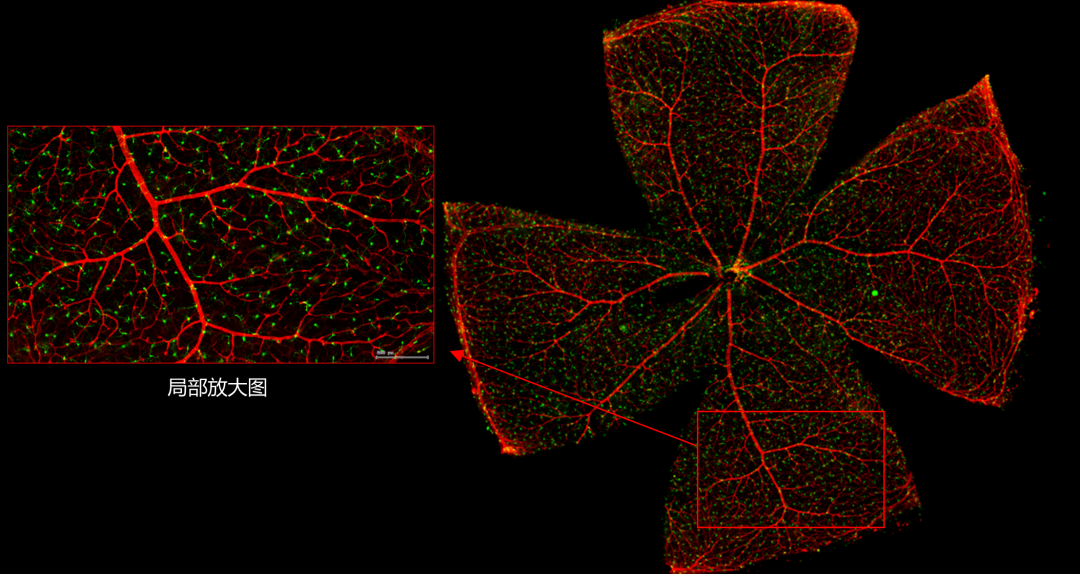

一般而言,眼底图像通常都是通过激光扫描成像进行采集,但是由于眼底可观测的视野往往是很有限的,一个患者的眼底信息需要多张扫描图像才能完全显示出来。这种局限性大大不利于病情进行全面的、细致的诊断。Tissue Cytometry全景组织流式定量分析技术进行全景图像获取,在单细胞、组织结构、细胞空间信息等多个层面进行定位、定性、定量分析。从而更好的对病变区域进行有针对性的跟踪观察和全面分析。

视网膜荧光样本中小胶质细胞胞体、神经纤维识别、血管识别、血管斑点识别、神经元与血管的距离分析。

1. 利用TissueFAXS系统进行玻片荧光的全景扫描。

2. 使用StrataQuest分析软件进行定量分析。

5. 识别血管的Texa Red染色区域面积及强度。

血管识别:根据Texa Red通道进行识别,并去除面积小的及非同一焦面的血管,仅对确定的清晰的同一焦面的大血管进行面积统计。

血管与小胶质细胞的距离0-0.1μm(红色框线标记)

血管与小胶质细胞的距离0.1-1μm(粉色标记)

血管与小胶质细胞的距离1-3μm(粉色标记)